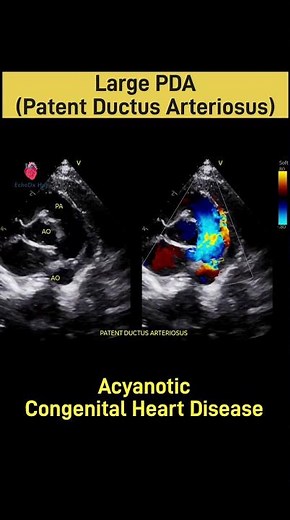

Echo Findings - PDA Echo

Echocardiogram - PDA

Echo - PDA

Long Axis View - PDA

Echo - Patent Ductus

Arteriosus - PDA

2D Echo - PDA

Echocardiography - PDA